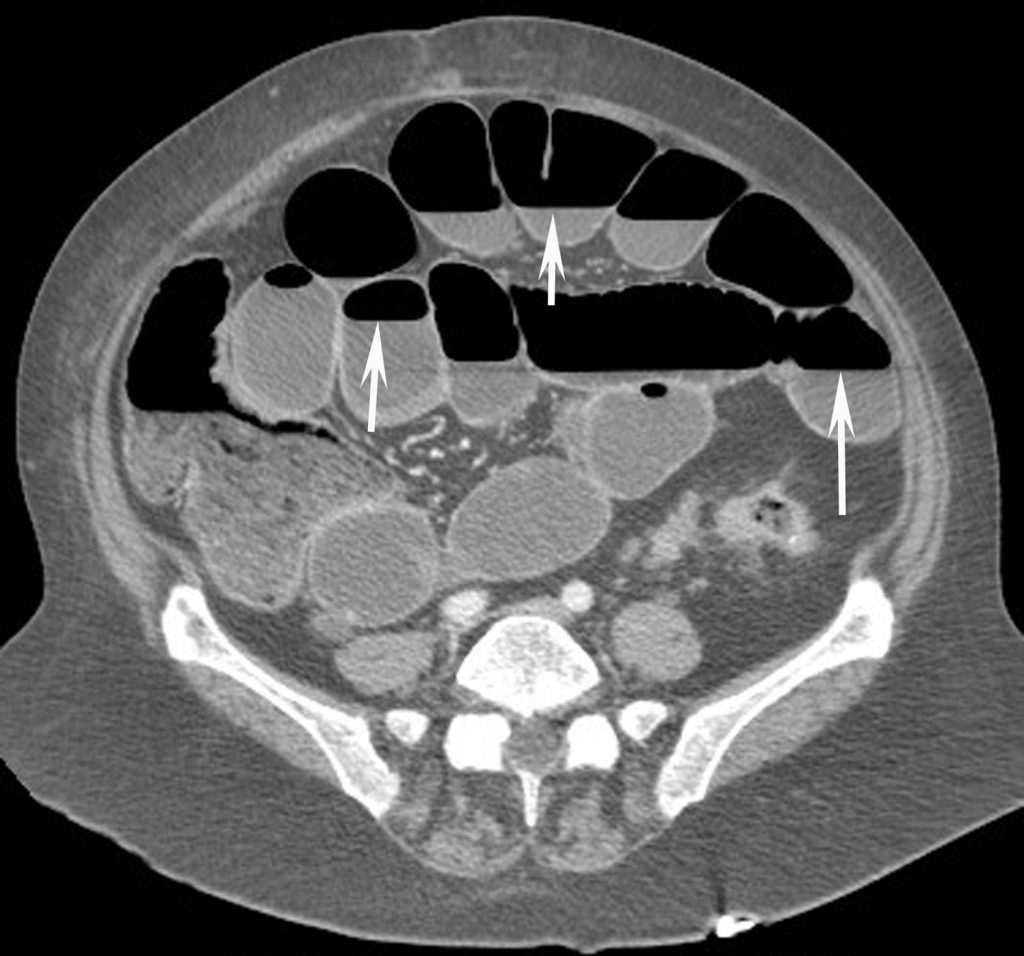

En amont du siège de l’occlusion, il met en évidence des anses digestives distendues sièges d’une stase liquidienne qui se traduit par la présence de niveaux hydroaériques (figure 14.1) ou par un contenu totalement liquidien des anses. La distension digestive signe le diagnostic. Lorsqu’il existe une distension de l’intestin grêle avec un diamètre des anses supérieur à 25 mm ou une distension du côlon supérieure à 80 mm de diamètre, alors le diagnostic d’occlusion est posé.

Fig. 14.1 Coupe tomodensitométrique axiale après injection de produit de contraste d’une occlusion du grêle montrant la distension avec stase hydroaérique des anses grêles qui présentent de nombreux niveaux hydroaériques (flèches) et un diamètre supérieur à 25 mm.

Source : CERF, CNEBMN, 2022.